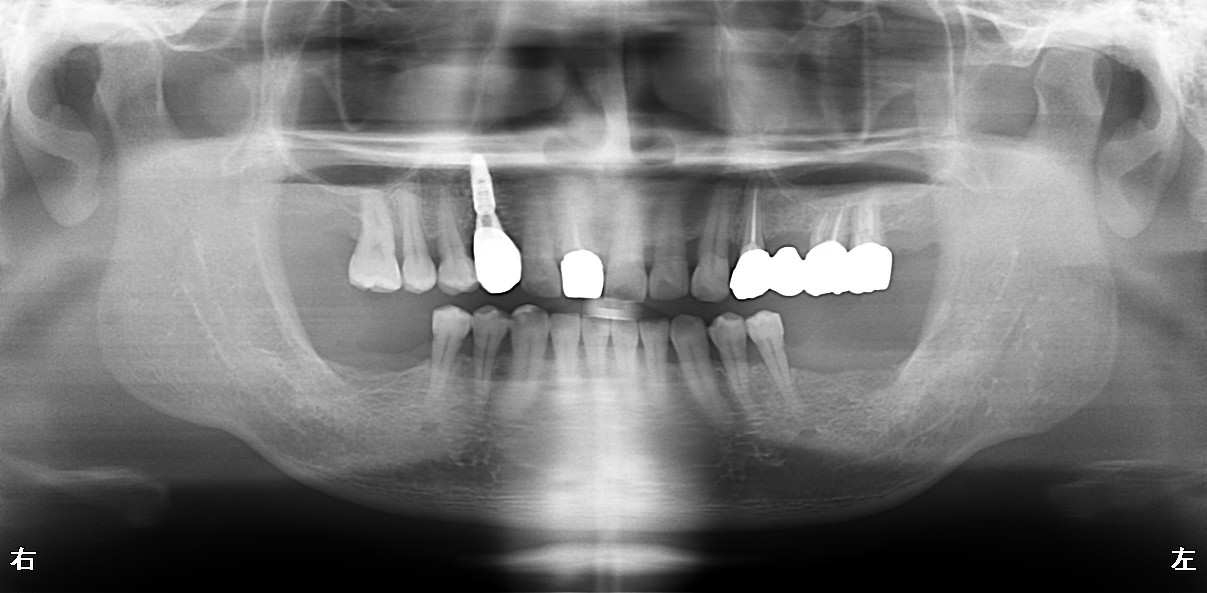

全体的に虫歯ができてしまっていた方の治療報告をさせて頂きます。

50代の男性の患者さんです。

虫歯のよりかみ合わせが崩壊してしまっています。

保存できない歯も多数ありました。

術前